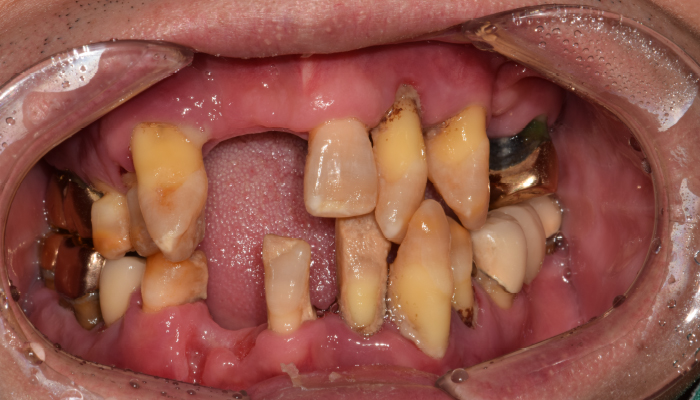

• 식립전

식립후